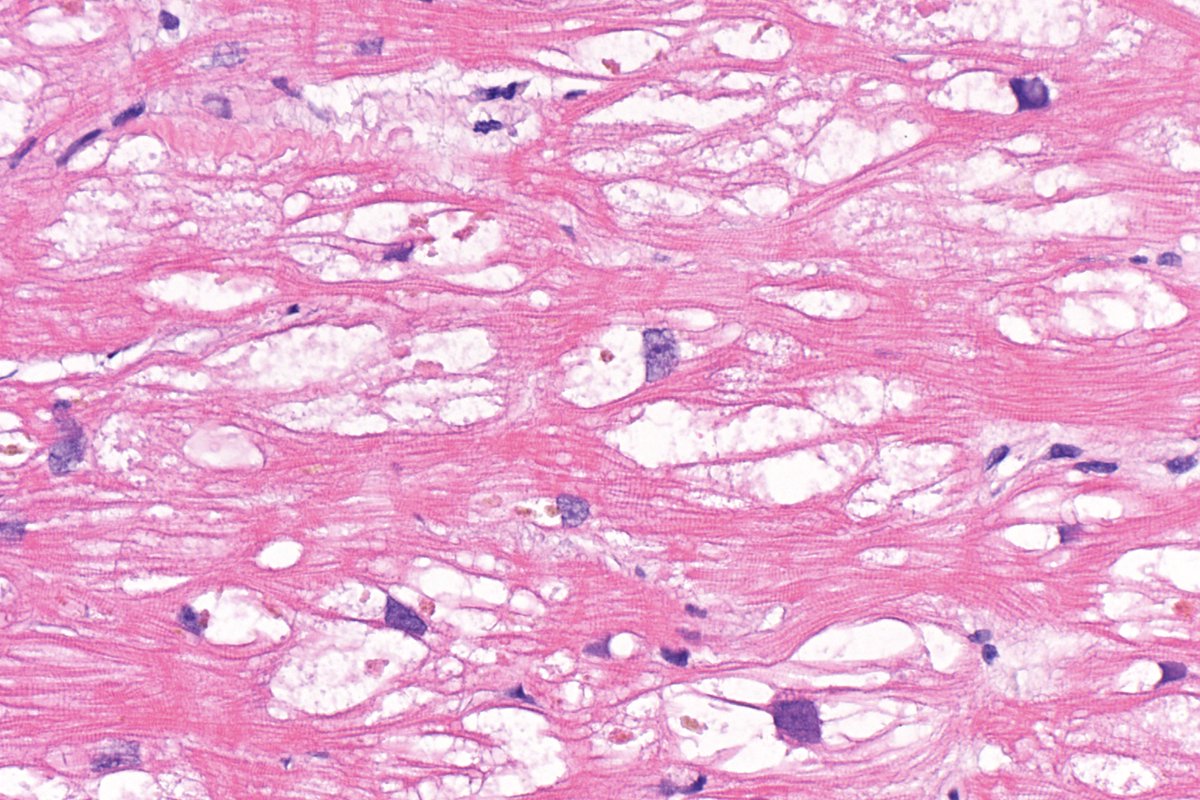

⁉️#GUpath #PEDIpath⚠️ 15YOB with a 7 mm intra testicular nodule... 🔪GROSS🔪 Woo Cheal Cho, MD GU Pathology Society (GUPS) Dr.Gauri Vidolkar MD Frank Ingram, MD Ankur Sangoi @evacomperat Daniel Skipper @AkgulMd Jonathan Zuckerman MD PhD Carla Ellis MD, MS Erasistrate Farshid Siadat, MD, FRCPC Francesca Khani, MD Peter Sadow, MD, PhD Ashish M. Kamat, MD, MBBS Nature Reviews Urology ⏭